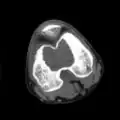

| Chondoblastoma of thigh bone near knee (CT scan, non-contrast) | |

1. a. X-ray of chondroblastoma of thigh bone near knee

1. b. CT scan shows chondroblastoma of thigh bone near knee more clearly

1. c. CT scan of chondroblastoma of thigh bone near knee (cross-section view)